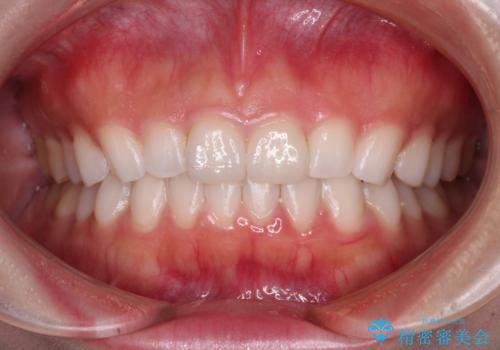

- 矯正治療で歯列を整えた後、前歯の形が気になった患者様です。

矯正前の歯列の影響で、前歯の先端が非対称にすり減ってしまったため、矯正治療後の形が非対称になっていました。

むし歯はなく、矯正治療で咬み合わせが改善していたので、侵襲量の少ないラミネートベニアにて治療することとしました。